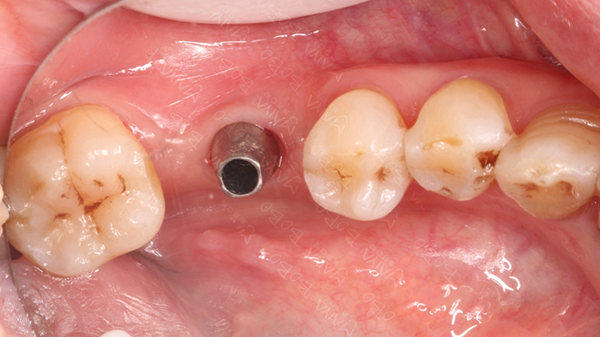

植入种植体

种牙完成后的牙齿

麦芽口腔种植医师团队对赵阿姨的情况全面分析,为其量身定制麦芽MAC数字化精确种植牙,通过模拟导航把握种植角度,深度,吻合度,准确快速找到最佳植入位置,稳固耐用可超过几十年。赵阿姨不停点赞:"儿子打电话帮我预约的,今天早早便催我出发,不忍辜负儿子的一片孝心,所以今天就过来了,没想到这里的条件这么好,医护人员都很热情很专业,环境一流,技术一流。"